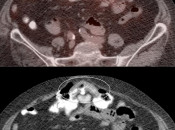

After the stomach, normal intense colon uptake is the most over-called “abnormality” by the inexperienced PET/CT radiologist.

The colon — focally or diffusely — often demonstrates intensely uptake of FDG.

Proposed mechanisms for colonic uptake of FDG include muscle contractions, the presence of lymphoid tissue and intraluminal contents.

The most common sites of normal physiologic intense colon uptake are the cecum and the distal rectum.

Generally, colonic uptake should be considered normal unless:

- There is an accompanying CT abnormality (e.g. focal bowel wall thickening or focal mass); or

- A solitary focus of intense uptake presents in an otherwise non-avid (or minimally avid) colon. Although this focal uptake may still represent normal physiologic uptake, it is reasonable to raise the possibility of a small polyp and recommend colonoscopy (polyps are rarely visible on the CT images).

We generally report, “As an adenomatous polyp or other pathology cannot be excluded, further evaluation with colonoscopy may be warranted, if not recently performed.”

Caveats:

Hemorrhoidal Inflammation:

Focal intense uptake in the ano-rectal region is a very common finding. It is considered normal in the absence of an associated soft tissue abnormality. It is often attributed to hemorrhoidal inflammation.

Be careful to not confuse ano-rectal uptake (typically representing hemorrhoidal inflammation) with rectal uptake (often malignancy).

Metformin:

This very popular medication is notorious for causing extensive and extremely intense bowel uptake (colon > small bowel). As this uptake can occasionally limit interpretation, we ask our patients to discontinue Metformin 24-hours prior to their exam.